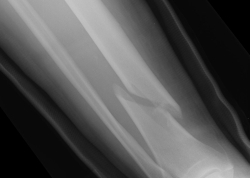

Nová liečba zlomenín

Pokroky vo vede sa odrážajú v každej oblasti medicíny. Najmarkantnejšie je to vidieť pri vývine nových molekúl a liekov. Zásadné novinky sa objavujú aj v časti medicíny, založenej na statike a biomechanike, typickej pre ortopédiu.

Veľká časť ortopedických chorôb sa dá vysvetliť na základe analýzy biomechaniky. Patria medzi ne aj zlomeniny. Zlomenina kosti je porušenie kontinuity kosti následkom násilia, ktoré kosť poškodilo. Typické zlomeniny, s ktorými sa bežne stretávame, sú traumatického pôvodu a vyvolané veľkým násilím. V ortopédii sa stretávame ešte so špeciálnymi typmi zlomenín, ktoré nie sú vždy vyvolané adekvátnym násilím a zaraďujeme ich medzi špeciálne typy zlomenín.

Liečba sa riadi prísnymi zásadami. Nové oceľové alebo titánové implantáty, ktoré sú dômyselne konštruované, nám súčasnú liečbu podstatne zlepšujú. Máme možnosť ich použiť aj na našich slovenských pracoviskách. Fraktúra je definovaná ako prerušenie kontinuity kosti následkom direktného alebo indirektného násilia. Fraktúra môže pozostávať z jednoduchej zlomeniny, z viacerých úlomkov, alebo môže obsahovať množstvo fragmentov (trieštivá fraktúra). Ak sa vytvorí len röntgenologická štrbina bez úplného oddelenia, hovoríme o fisúre.

Fraktúry sa posudzujú z hľadiska pôvodu, mechanizmu vzniku, stupňa straty kontinuity, ďalej podľa priebehu lomovej línie a podľa počtu úlomkov. Mechanizmus úrazu je dôležitým kritériom na posúdenie fraktúry, pretože podľa neho možno posudzovať aj eventuálne ďalšie poranenia mäkkých štruktúr. Fraktúry v detskom veku posudzujeme podľa mechanizmu vzniku a tiež podľa ich formy, kvôli určeniu optimálneho terapeutického plánu. Zvláštny význam má určenie zlomenín v oblasti rastových zón. Pretože zlomeniny sú závažné poškodenie zdravia, považujeme ich za urgentné stavy, ktoré treba okamžite liečiť.